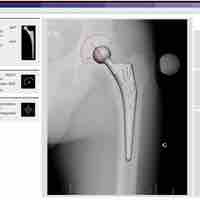

Arthroplasty

Arthroplasty is an operative procedure in which the arthritic or dysfunctional joint surface is replaced or repaired.